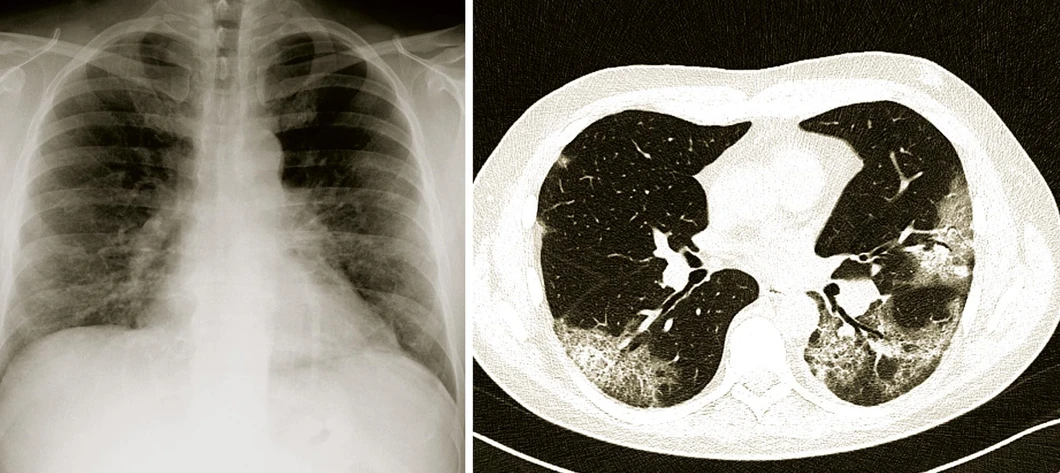

Závažnost nemoci závisí na míře plicního postižení. V akutním stavu je možné velikost plicního postižení zjistit jednak rozsahem rtg nálezu (obr. 1), jednak měřením oxygenace krve; jednoduché čidlo připojené zevně na prst nebo na ušní boltec dokáže sledovat, zda je krev v kapilárách dobře prokysličena. Při nedostatečném sycení se pacientovi podává kyslík maskou nebo nosními brýlemi. Jestliže to nestačí, mluvíme o těžkém průběhu nemoci covid-19. Pak je nutné pacienta přesunout na oddělení intenzivní péče a zahájit neinvazivní nebo invazivní ventilaci, případně ho napojit na přístroj zajišťující mimoplicní výměnu plynů (ECMO, extracorporal membrane oxygenation). Nebezpečnost plicního zánětu tím však není vyčerpána. Po odeznění akutní fáze může dlouhodobě přetrvávat zvýšená dráždivost průdušek, která vede k záchvatům dušnosti a kašle. Vzácně může nastat i nevratná vazivová přestavba plic (fibróza), omezující dýchání tím, že brání rozpínání plic při vdechu.

Vesmír/Radiodiagnostická klinika Nemocnice Na Bulovce: Snímky plic provedené různými technikami u téhož pacienta s těžkým průběhem nemoci covid-19. Na prvém obrázku (vlevo) je klasický Rtg snímek hrudníku, kde je oboustranně v dolních polích plicních lehce snížená transparence a zvýšená bronchovaskulární kresba – poměrně mírný rozsah tohoto nálezu dostatečně nekoresponduje se závažností respirační insuficience. Druhý snímek (vpravo) získaný počítačovou tomografií (CT) ukazuje neostře ohraničené okrsky tzv. „opacit mléčného skla“ a „crazy paving“, které jsou typické pro plicní postižení při nemoci covid-19. Tento nález lépe osvětluje těžký průběh onemocnění.